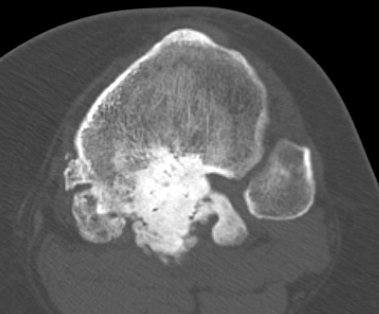

CT

Can be used to differentiate from osteochondroma

1. Parosteal OS

- attached to cortex growing into soft tissue

- normal cortex intact

2. Osteochondroma

- cortex of bone becomes cortex of osteochondroma

- medullary canal confluent with osteochondroma

- posterior femur rare